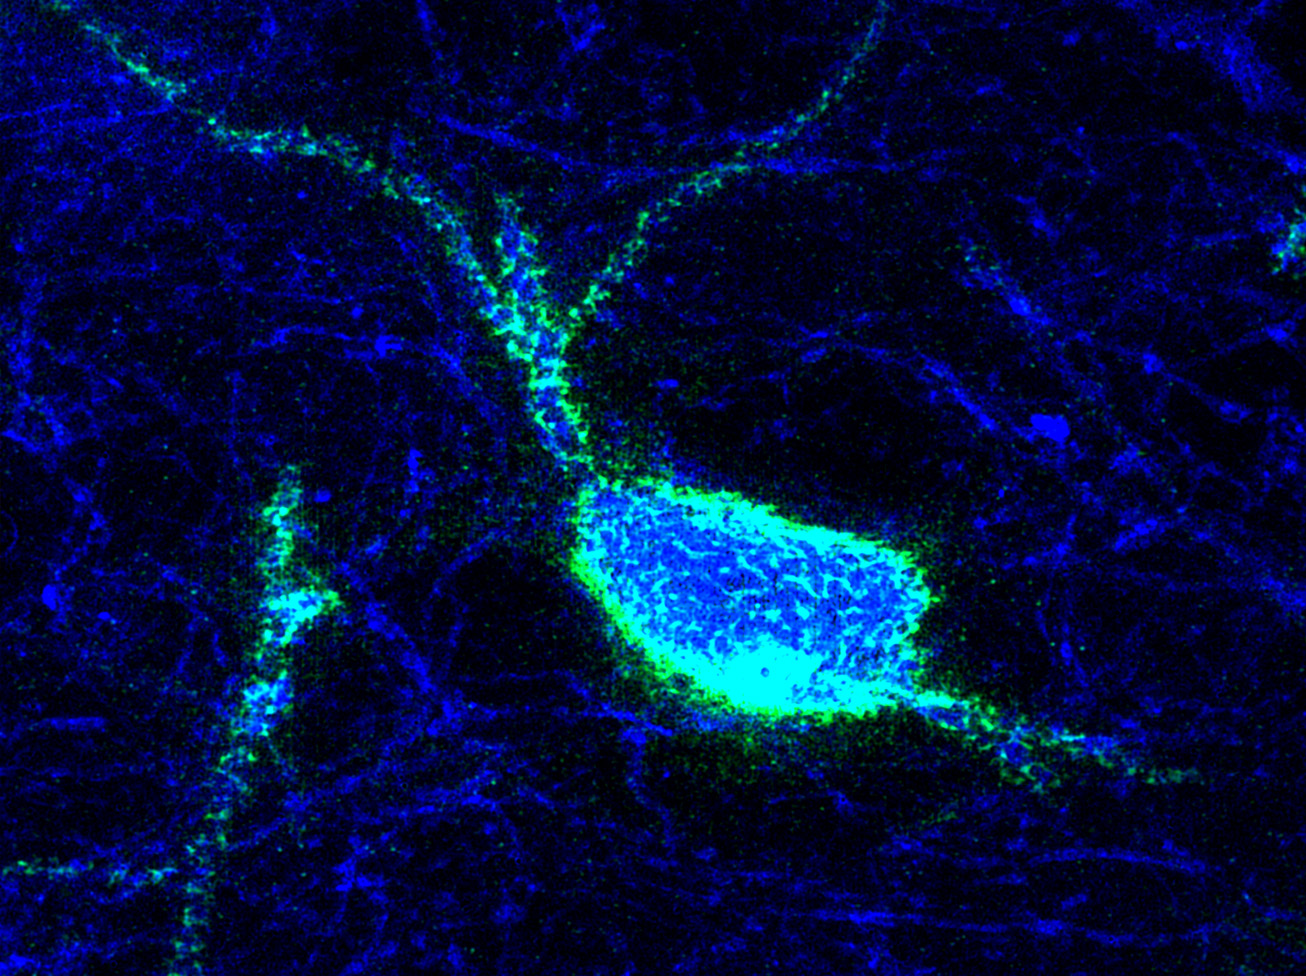

The project tackles its main objective using a multidisciplinary and translational approach. We will use animal models of adverse experiences using transgenic mice, combining molecular, structural and connectivity analyses with superresolution microscopy, behavioral tests and transcriptomics. The project also includes analyses of the thalamus of patients using postmortem tissue. Clinical studies will be also performed in living patients using psychological evaluations, expression analysis in blood and in olfactory neurons of genes relevant to thalamic function/plasticity and DNA methylation analysis of candidate genes. We also plan to generate IPSC cells from patients and, through a collaboration, generate thalamic organoids to study gene expression and connectivity. We will also analyze neuroimaging data in structural and functional MRI from patients to determine changes in different thalamic nuclei, as well as in their projecting regions in the cerebral cortex. Finally, we will perform correlation analyses of all neuroimaging, gene expression, epigenetic and organoid data. The project will be performed both in its basic and its clinical parts on males and females.